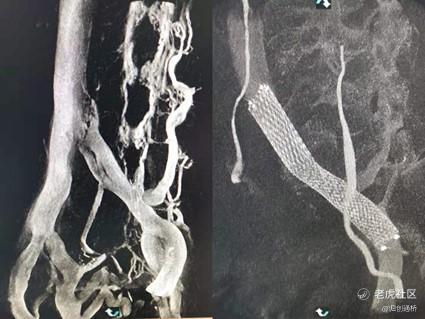

日前,由归创通桥发起的Zynlastic™静脉支架系统全国前瞻性、多中心、随机对照临床试验,在全国多家权威临床中心共同协作下,顺利完成全部161例受试者入组。试验自主研单位启动到全部完成入组,仅用时10个月,显示出令人振奋的初步成果:Zynlastic™静脉支架的器械成功率与手术成功率均达到100%;已实现随访6个月的受试者中,无一例出现支架再狭窄或血运重建。产品品质和性能优异,符合临床要求;临床随访预期将达到媲美进口产品的性能与中长期治疗效果。

Zynlastic™静脉支架应用于髂静脉压迫综合征的治疗

病例及影像©重庆医科大学附属第一医院